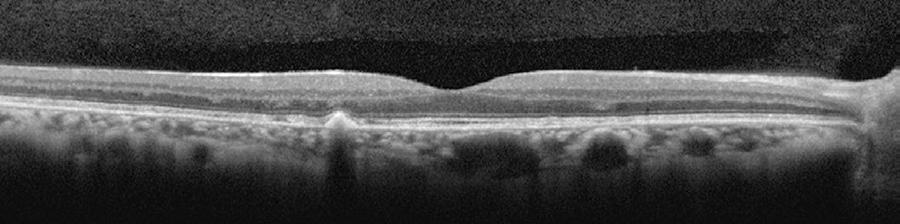

Only mild visual acuity loss was detected, with best-corrected visual acuity of 20/25 in the right eye and 20/30 in the left eye. Pupillary direct and consensual light reflexes were normal and ocular motility was preserved. Intraocular pressure was within the normal range: 14 mmHg in the right eye and 15 mmHg in the left eye (Goldmann). Slit lamp biomicroscopy revealed transparent cornea and lenses with no noteworthy structural changes. The fundus presented multiple round yellowish flecks at the level of the retinal pigment epithelium scattered at the posterior pole. Some of these flecks were elongated and showed partial confluence with neighboring flecks (Figure 1). Imaging was performed with a Spectralis HRA + OCT (Heidelberg Engineering, Heidelberg, Germany). Areas of increased fundus autofluorescence (FA) were noted, with surrounding borders of decreased FA intensity, corresponding to the visible yellowish fundus lesions (Figure 2). Spectral domain optical coherence tomography (SD-OCT) showed elevated lesions along the retinal pigment epithelium (RPE)/ Bruch complex, preserving the external limiting membrane (Figure 3).

Figure 3 Spectral domain optical coherence tomography [SD-OCT] showing elevated lesions located along the retinal pigment epithelium (RPE)/Bruch complex and preserving the external limiting membrane.

On SD-OCT, the presence of elevated lesions along the RPE/Bruch complex, corresponding to areas of increased FA without atrophy of the RPE/Bruch complex and the inner and outer segment (IS/OS) layer, also differ from the findings in Stargardt disease and fundus flavimaculatus(9-11).